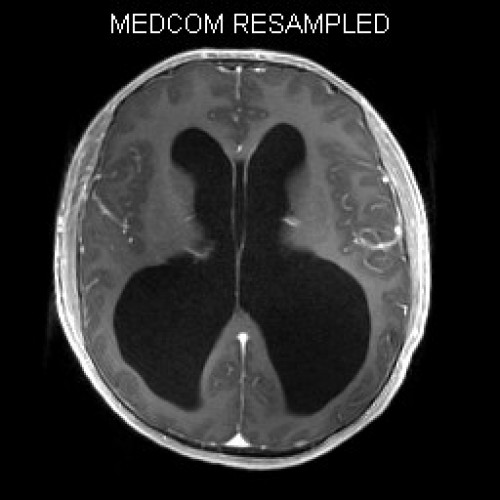

ICD: C75.3

ICD: G91.9

12-jähriger Junge. Die Eltern werden zu einem Gespräch bei der Klassenlehrerin gebeten, weil ihr Sohn sehr unaufmerksam geworden sei und seine Leistungen in der Schule bedenklich abgenommen hätten. Er droht das Klassenziel der 6. Klasse nicht zu erreichen.

Den Eltern war seit längerer Zeit bereits aufgefallen, dass sich ihr Sohn nach der Schule am liebsten ins Bett lege, um für eine Stunde einen Mittagsschlaf zu halten.